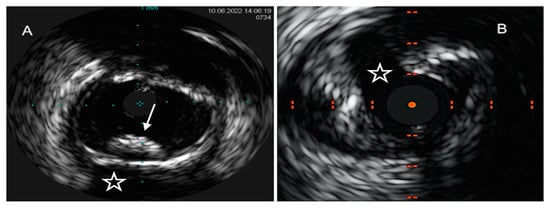

4.1. Intravascular Ultrasound